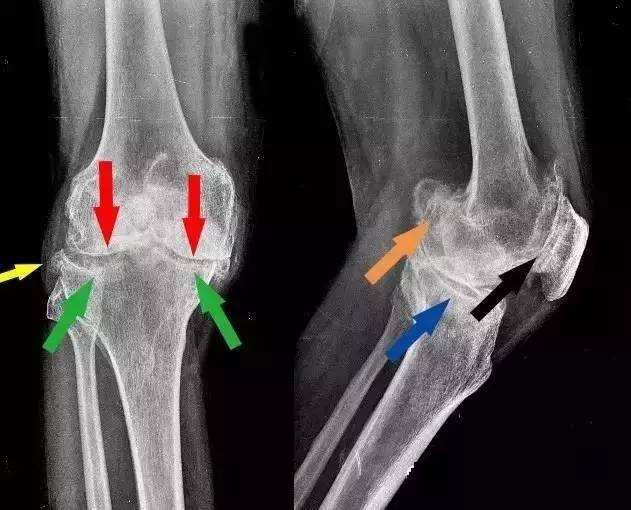

尤其是腰疼脖子疼膝盖疼,一拍片子,嘿!腰椎颈椎还真有骨刺,没准了,就是它了。再加上一些医术不精或别有用心的医生在旁边推波助澜的告诉患者,“你看,片子上有骨刺了,你的病就是这个骨刺引起的。但你不用担心,用了我的药就能让这骨刺消失。”

2、骨刺,只是X光片上看起来很尖,实际上并不是

是的,虽然X光片上看骨刺都是尖尖的,好像尖刀一样,但实际上,骨刺并不是尖的,而是钝的。

骨科医生在做手术时都会知道,那些在X光片上看起来尖尖的骨刺,在切开后会看到,其实骨刺表面包着一层圆润钝钝的软骨或结缔组织。只是这层圆润钝钝的软骨和结缔组织在X光片上不显示,只显示下面的骨头,所以尽管在片子上看骨刺好像是尖尖的,但是其表面其实是包着一层圆润的软骨的,并不会扎伤什么。

尽管大多数情况下骨刺并不会影响我们的生活工作,但是如果骨刺长的位置不好,或者“个头”长得过分了,如果碰巧压迫刺激到了旁边没多远的重要结构,比如:重要的血管、神经、脊髓等,这时骨刺就变的不那么美好。也只有这个时候才需要治疗,甚至手术。当然,这种情况其实非常非常少见。